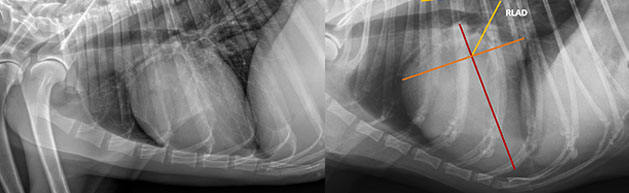

Curso Online de Diagnóstico Radiológico (Patologías Abdominales)

Amalia Agut

Jefa del Servicio de

Diagnóstico por Imagen del

Hospital de la Univ. Murcia

Curso Online de Diagnóstico Radiológico (Patologías Torácicas)

Marta Soler

Miembro del Servicio

de Diagnóstico por Imagen del